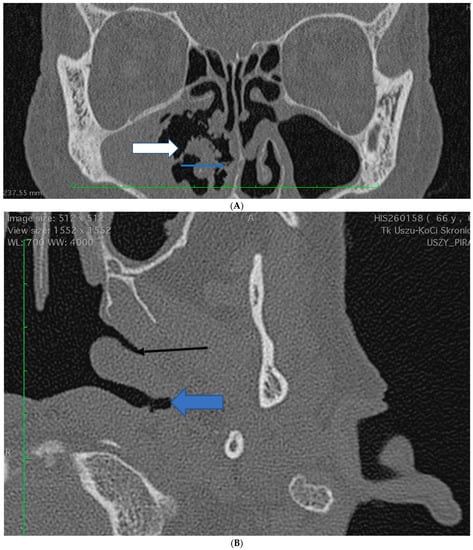

2.2. Case 2